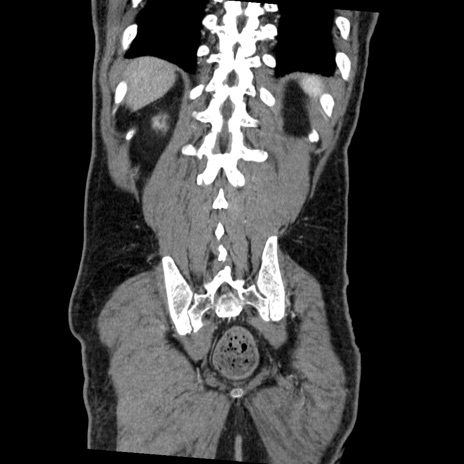

症例22(冠状断像)

【症例】50歳代男性

【主訴】腹痛

【現病歴】AVMからの被殻出血のため回復期リハ病棟入院中。 本日午後3時頃急に下腹部痛が出現した。

【既往歴】AVM、被殻出血、虫垂炎、高血圧

【身体所見】意識晴明、左半身不全麻痺、会話の理解は良好、36.5°C、腹部:膨隆、全体に板状硬、下腹部正中に圧痛点あり、反跳痛-、筋性防御不明、右下腹部にope scar

【データ】WBC 9400、CRP 0.06